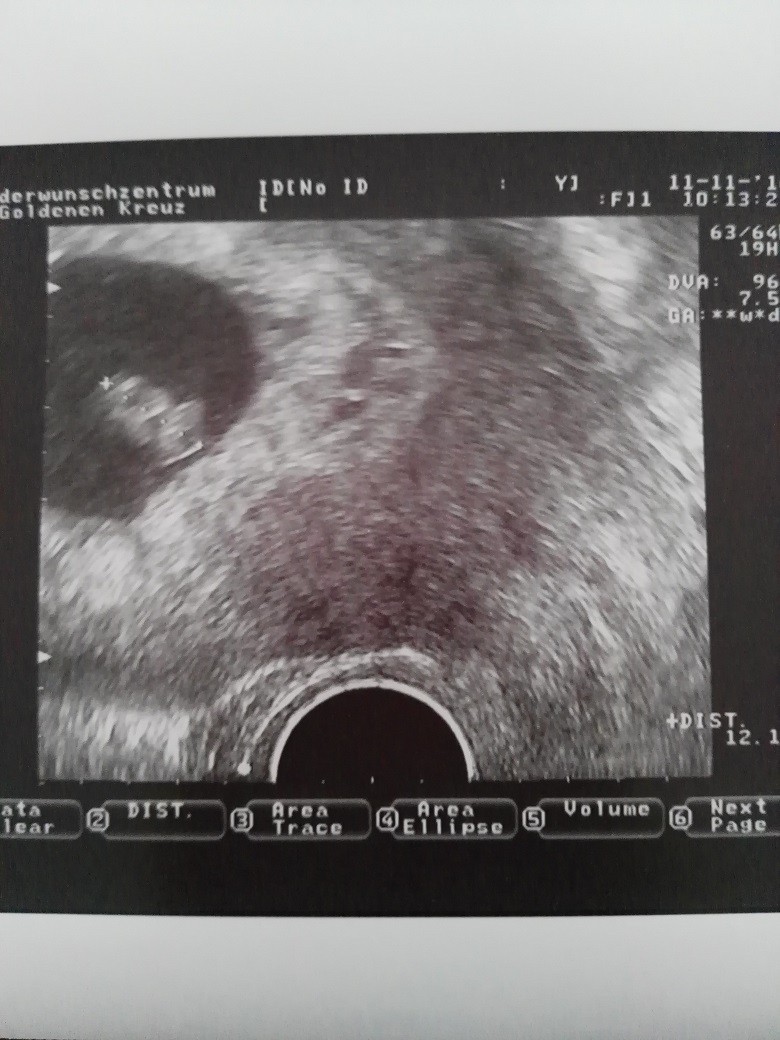

Jest! [emoji176][emoji176][emoji176]

Szczęście ma 12 mm, wszystko prawidłowo się rozwija.

Dziękuję Wam za kciuki i życzenia. Mam nadzieję, że każda z Was przeżyje tę cudowną chwilę.